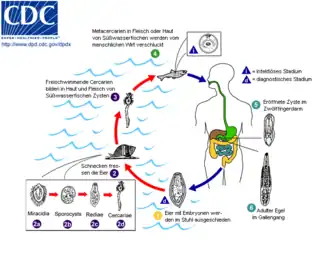

Bestimmte Parasitenerkrankungen der Leber sind ebenfalls Risikofaktoren für das Gallengangskarzinom. Der in Thailand, Laos und Malaysia verbreitete Leberegel Opisthorchis viverrini und sein vor allem in Japan, Korea und Vietnam beheimateter Verwandter Clonorchis sinensis erhöhen das Erkrankungsrisiko für das Gallengangskarzinom.[11][12][13] Patienten mit chronischen Lebererkrankungen wie Virushepatitis B oder C,[14][15][16] einer alkoholischen Lebererkrankung oder Leberzirrhose anderer Ursache erhöhen ebenfalls das Risiko für ein Gallengangskarzinom.[8][17]